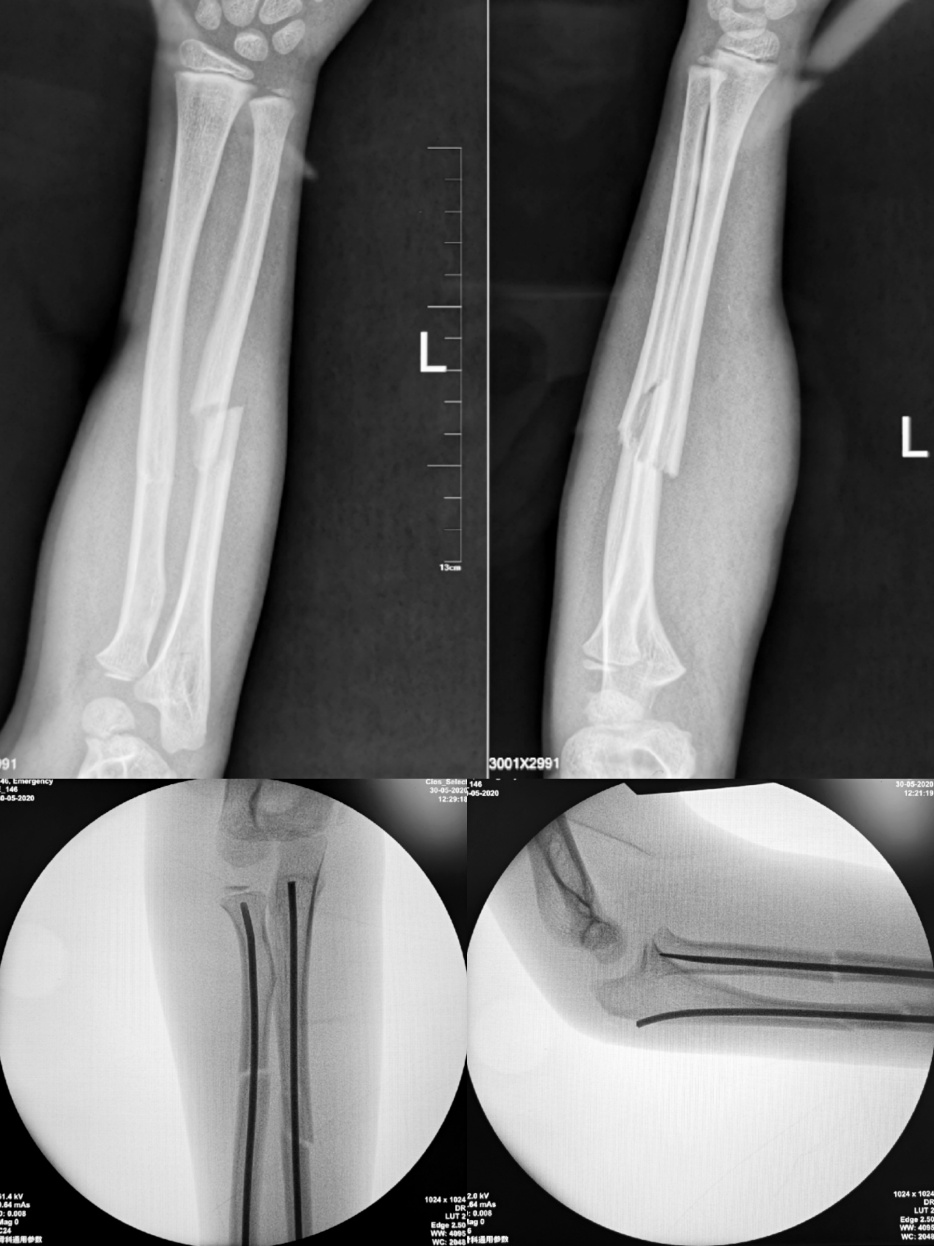

患儿,男性,12岁。因摔倒致左前臂肿痛伴活动受限2天,入院诊断为左侧孟氏骨折。入院后,进一步做详细检查后发现患儿左前臂及肘关节周围肿胀明显,压痛(+),左前臂旋转及屈伸活动均明显受限,患肢X线片示:1、左尺、桡骨干骨折;2、左桡骨头半脱位。

陈永刚医生带领县医院医护人员经过术前检查及病例讨论后,制定了一系列详细周密的诊疗计划,在向患者及家属详细讲解手术的必要性和可行性后,家属表示理解和支持。5月25日,在陈永刚医生的带教下,县医院骨科医师团队成功完成“左孟氏骨折闭合复位经皮ESIN内固定术”。手中一切顺利,术后患儿病情平稳,现已顺利出院。